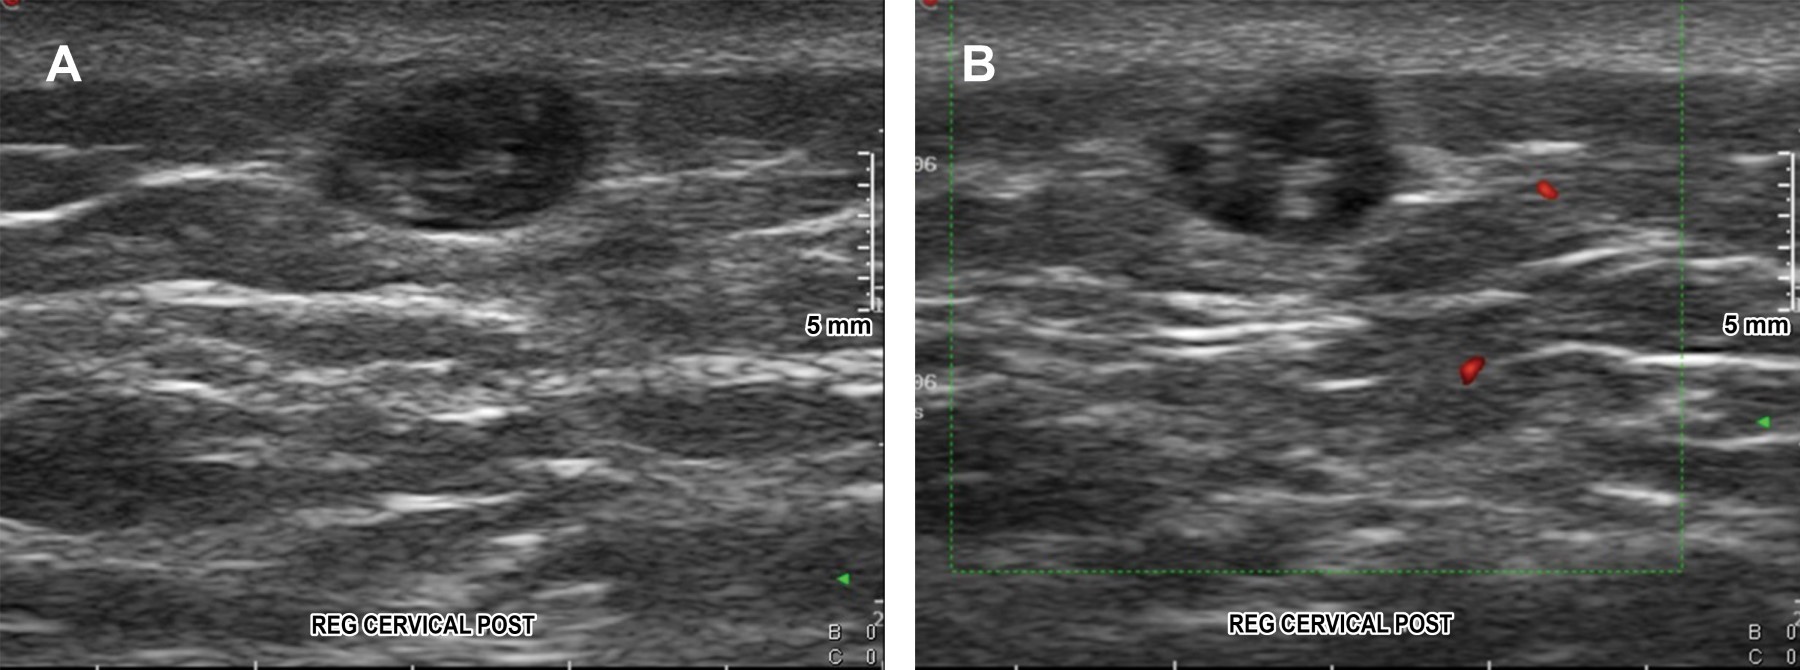

Filariasis is a group of parasitic diseases mainly affecting the lymphatic system and skin, produced by nematodes of the Filarioidea family. There are almost 200 different types of filaria worldwide and just a few parasitizing human beings. Transmission being through insects as a vector. Filariasis are considered as "neglected diseases" by the World Health Organization. Diagnosis is made by demonstrating microfilariae in circulating blood or skin where it can be visualized with auxiliary imaging methods. Although mortality is low, the morbidity associated is not only for the physically disabilities, but also mental, social, and financial losses that contribute to stigma and poverty. In this article, the case of a 63 years old man with onchocercal filariasis is presented, evaluating live parasites by scanning a cutaneous nodule in the nape with an evolution of four years histologically documented.

Figure 1